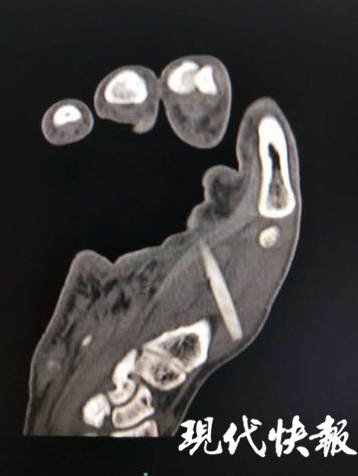

△医生从伤者右手掌心处取出一截长约 5 厘米的断裂筷子

随后,饭店老板紧急前往betway在线登陆,经医生诊断,伤者手背鼓起,断裂的筷子已完全刺进伤者的手掌肌肉中。经过两个小时的紧急手术,伤者受伤部位修复完毕,医生从其右手掌心处取出一截长约 5 厘米的断裂的筷子。